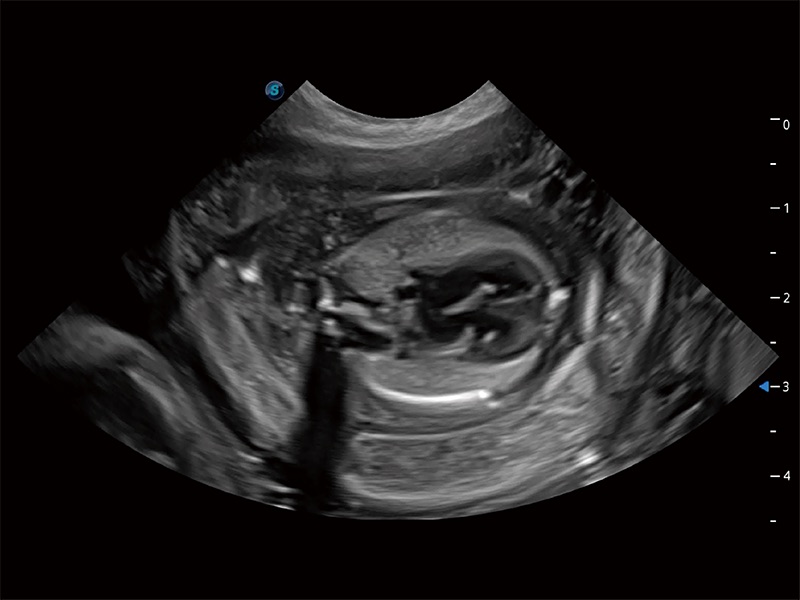

ProPet 80 全新的動物超聲智能軟件和豐富的探頭群,為動物醫(yī)生提供了高清晰度和精細分辨率的圖像,無論在寵物、馬科、畜牧還是實驗室動物等應(yīng)用中都可以輕松應(yīng)對,為您的日常工作帶來滿意的體驗。